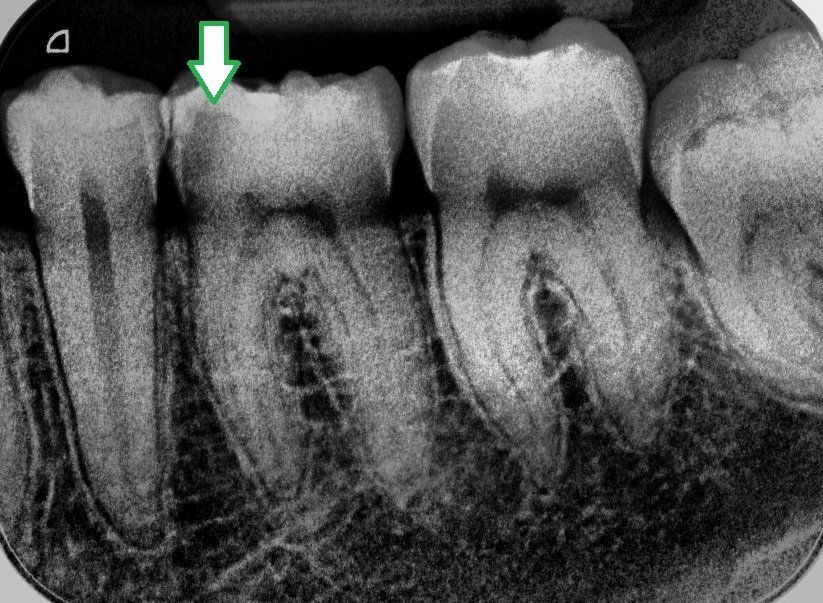

Das selbe Bild wie oben links. Durch Veränderung des Kontrastes kann bei digitalen Röntgenbildern die Diagnostik verbessert werden. Die Karies (siehe Pfeil) ist nun noch deutlicher zu sehen.

Die digitale Bildauswertung bringt weitere Vorteile: Wir können Bilder vergrößern, verschiedene Filter zur Diagnostik einsetzen, digitale Vermessungen vornehmen und unsere Bilder in exzellenter Qualität digital an Kollegen schicken, die diese Bilder dann in gleicher Weise analysieren können.